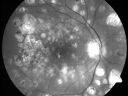

72-year-old man had macular and peripheral laser done in the past(1980's)(25 years ago). I have been seeing him for years now and I have not done any treatment. He takes Alphagan for his glaucoma. He was last here two years ago and he noticed his vision, although limited, seems about stable to him. He is diabetic for 30 years.

VISUAL ACUITY: Vision OD is 20/160, OS is 20/160. IOP: OD 15, OS 14. Posterior chamber intraocular lens is in good position in both eyes.

OD: Vertical C/D ratio is 0.5. There is extensive macular and peripheral scarring.

OS: Vertical C/D ratio is 0.5. There is extensive macular and peripheral scarring.

PHOTOGRAPHS: Photos confirm clinical findings.

FLUORESCEIN ANGIOGRAPHY: FA shows predominantly hypofluorescence corresponding to the laser spots and geographic atrophy. There is no staining or leakage in either eye nor is there any sign of any diabetic retinopathy.

Macular and Peripheral Retinal Scarring from Diabetic Laser Done 25 years previously845 views72-year-old man had macular and peripheral laser done in the past(1980's)(25 years ago). His vision, although limited, seems about stable to him. He is diabetic for 30 years. OD is 20/160, OS is 20/160.     (0 votes)